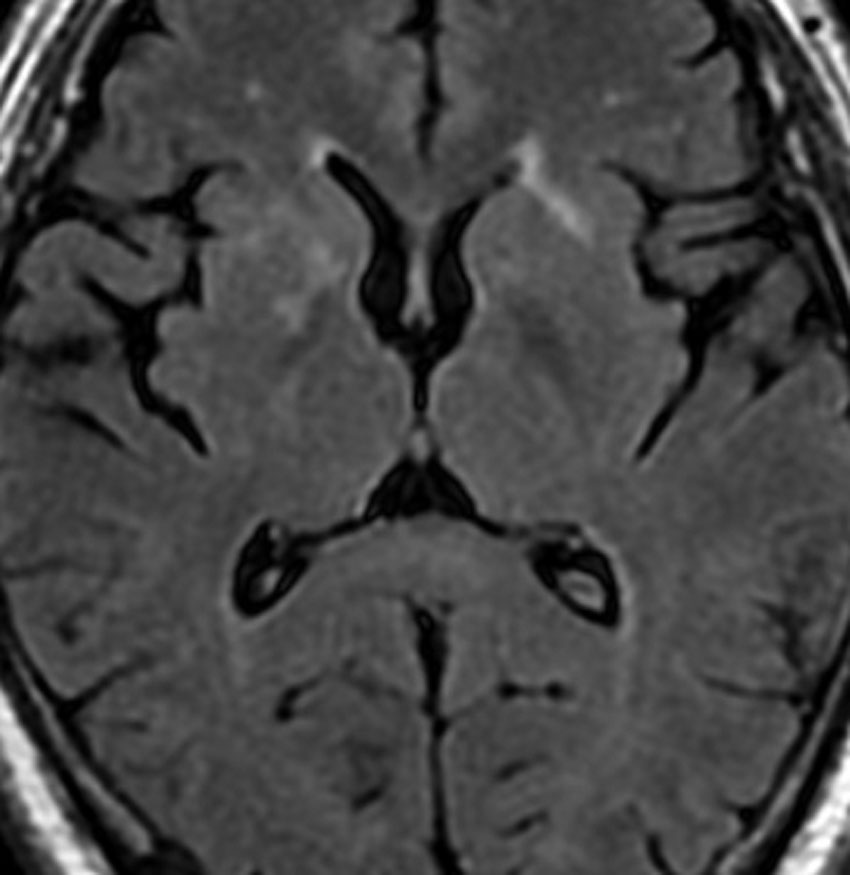

アレビアチン(フェニトイン)やデパケン(バルプロ酸)を何年も服用していると小脳に萎縮がくることがあります。小脳失調症というふらつきがでることは少ないのですが,MRIで小脳が小さくなったようにみえます。

20年以上バルプロ酸の服用をしている患者さんです。左と中央のMRIでは小脳萎縮がありますが,右側の大脳では萎縮は全くありません。小脳症状はありません。